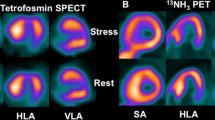

In this quite heterogeneous scenario of anatomical, physiopathologic, and clinical manifestations, the importance of vascular abnormalities and myocardial ischemia in HCM has constantly increased since the time of their first detection [16, 33]. According to the different modalities and criteria used to define the presence of ischemia in HCM, its incidence ranges from approximately 20% to over 60% of patients, with an average just below 50% [34••]. The structural abnormalities in the small vessels of HCM patients, such as vessel wall thickening, with prevalent media participation and lumen restriction, and reduction in capillary density, have been convincingly demonstrated [16, 17, 35,36,37,38]. Together with the direct vessel involvement, other tissutal disease-related abnormalities, such as fibrosis, may contribute to ischemia in HCM [15, 39, 40]. Autoptic studies had identified signs of prior necrosis in HCM patients [33, 41, 42]. The relatively frequent occurrence of chest pain is well known, and several reports demonstrated the presence of myocardial perfusion abnormalities [23, 43,44,45,46,47,48]. These abnormalities were initially related to the presence of epicardial coronary artery disease, and the current guidelines still include the use of myocardial perfusion imaging for ruling out coronary artery disease in HCM [5]. However, the negligible role of epicardial vessel stenosis in causing the ischemic changes and symptoms in HCM patients was clear very early. Already in 1979, Rubin et al. had tested the usefulness of thallium-201 for ruling out coronary artery disease as the cause of anginal symptoms in HCM: in their study, 9/10 patients with normal coronary angiograms had indeed normal stress perfusion, but one showed a significant exercise-induced defect [43]. One year later, Pitcher et al. identified various patterns of stress and rest perfusion abnormalities in thallium-201 scans performed in HCM patients, who had normal vessels in coronary angiography in the large majority of cases [44]. In a larger patient cohort, thallium-201 single-photon emission computed tomography (SPECT) registered perfusion abnormalities, mainly stress-induced, in 41 of 72 patients, and the authors interpreted the data as the demonstration of a dynamic ischemic process that contributed to the clinical symptoms [45]. The concept was reinforced by another study that showed the reduction of stress-induced perfusion defects in HCM patients after verapamil therapy [46]. Cannon et al. demonstrated that the stress-induced perfusion defects were related to the occurrence of true ischemia, as shown by lactate extraction, in the majority of cases, and for the first time suggested a more severe impairment of the subendocardium, because of the several patients with transient ischemic dilation [47]. The importance of subendocardial ischemia in HCM was also emphasized by a study by Yoshida et al., who identified a close relation between the occurrence of transient ischemic dilatation and an abnormal blood pressure response to exercise [48].

Taken together, all these studies converged in indicating microvascular disease as the main determinant of perfusion abnormalities in HCM. However, a direct evidence of abnormal myocardial blood flow (MBF) without epicardial vessel disease in these patients could be achieved only by performing the quantitative measurement of MBF by means of perfusion positron emission tomography (PET) [49] (Figs. 1 and 2). This imaging modality is nowadays getting a growing role in the clinical arena, also because of the wider diffusion of PET facilities and the major technical advances, but for many years, its main contribution was to help expanding our knowledge of disease physiopathology, and in this regard, HCM was a favorite field of utilization [50]. Camici et al. published the first demonstration that patients with HCM had an abnormal response to coronary vasodilation in 1991 [51]. While the finding of impaired maximal MBF in hypertrophied walls could be expected on the basis of the abovementioned anatomical abnormalities, already in this very early report, the complexity of microvascular involvement in HCM was apparent, because the authors found some degree of impairment even in the normal, nonhypertrophied walls [51]. Therefore, the study supported the concept that microvascular dysfunction is an early phenomenon in HCM and not just a late consequence of the anatomical changes, in particular fibrotic substitution [51]. The same group published various other studies in HCM patients aimed to confirm and better delineate the role of microvascular dysfunction in the disease. Gistri et al. demonstrated that verapamil did not significantly improved maximal MBF in HCM as compared to placebo; however, it favorably affected subendocardial perfusion, in partial agreement with the visual changes detected by thallium-201 SPECT [46, 52]. This finding was confirmed by a later study that showed an improvement in the subendocardium/subepicardium MBF ratio after verapamil treatment, although the average wall value was not significantly modified [53]. Lorenzoni et al. showed that there was no significant difference in resting and maximal MBF, and in myocardial flow reserve (MFR) in HCM patients with versus those without history of syncope or of nonsustained ventricular tachycardia [54]. Conversely, the same authors demonstrated that HCM patients with systolic dysfunction had a lower maximal MBF and MFR, and that there was an inverse relation between these parameters and the severity of the New York Heart Association class [55]. These reports suggested a potential clinical role of the assessment of microvascular dysfunction using quantitative PET for evaluating HCM severity and for patient prognostication [55]. Indeed, just few years later, the first demonstration of the clinical value of microvascular dysfunction assessment was published, as reported below, contributing to establishing the role of ischemia in HCM [22]. The large majority of the studies devoted to the definition of microvascular involvement, however, were still focused to improve the physiopathologic characterization of HCM.